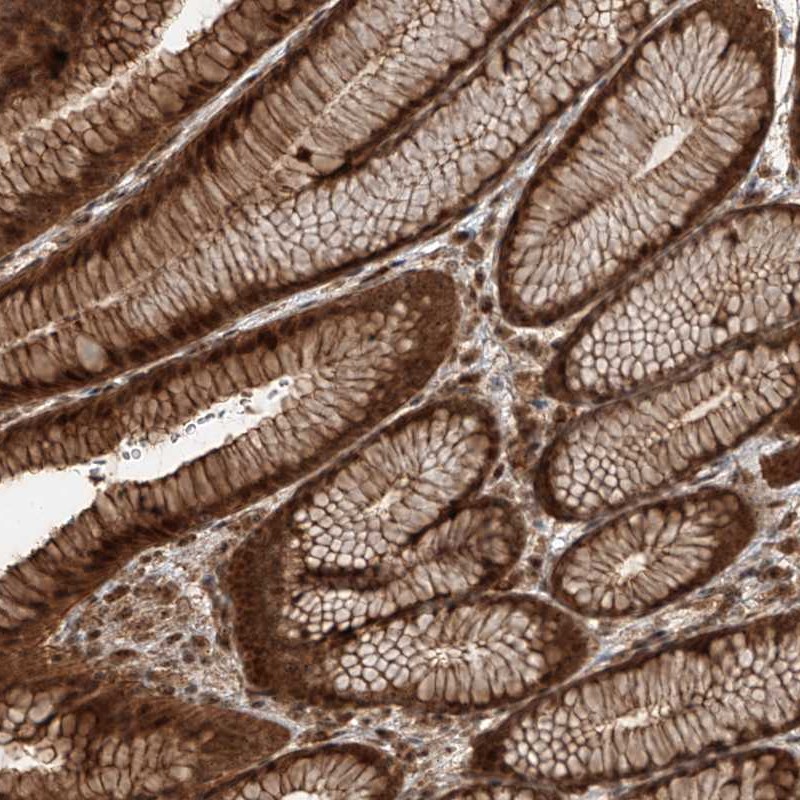

Immunohistochemical staining of human stomach shows strong cytoplasmic and nuclear positivity in glandular cells.